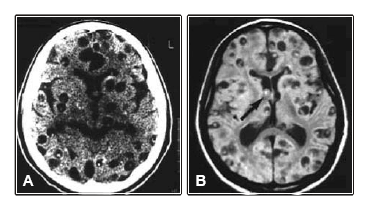

Um homem de 40 anos, imunocompetente, previamente hígido, é atendido no pronto socorro por ter apresentado primeiro episódio de convulsão focal que se generalizou. A tomografia de crânio sem contraste e a ressonância magnética mostram:

O diagnóstico mais provável é de